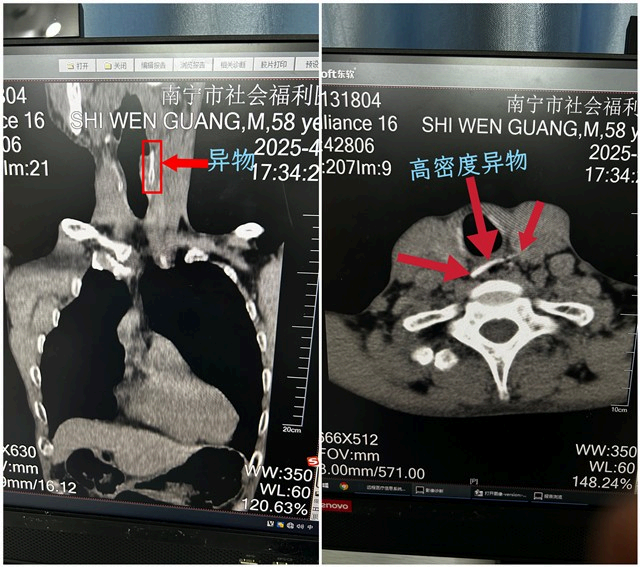

日前,精神科患者小施(化名)于晚餐期间突发剧烈呛咳、呼吸窘迫。接诊医师高度怀疑食道异物梗阻,随即启动应急流程,将患者紧急送至放射科进行CT检查。放射科团队迅速响应,检查发现其胸椎第1-2椎体层面食管内存在一条状高密度异物影,呈左下至右上斜行,且影像提示异物两端可能已刺穿食管壁,病情风险显著。放射科医师立即整合临床信息与影像细节,明确作出“食道骨性异物存留”的诊断,并在第一时间将精确的影像报告及危急值通知临床科室。